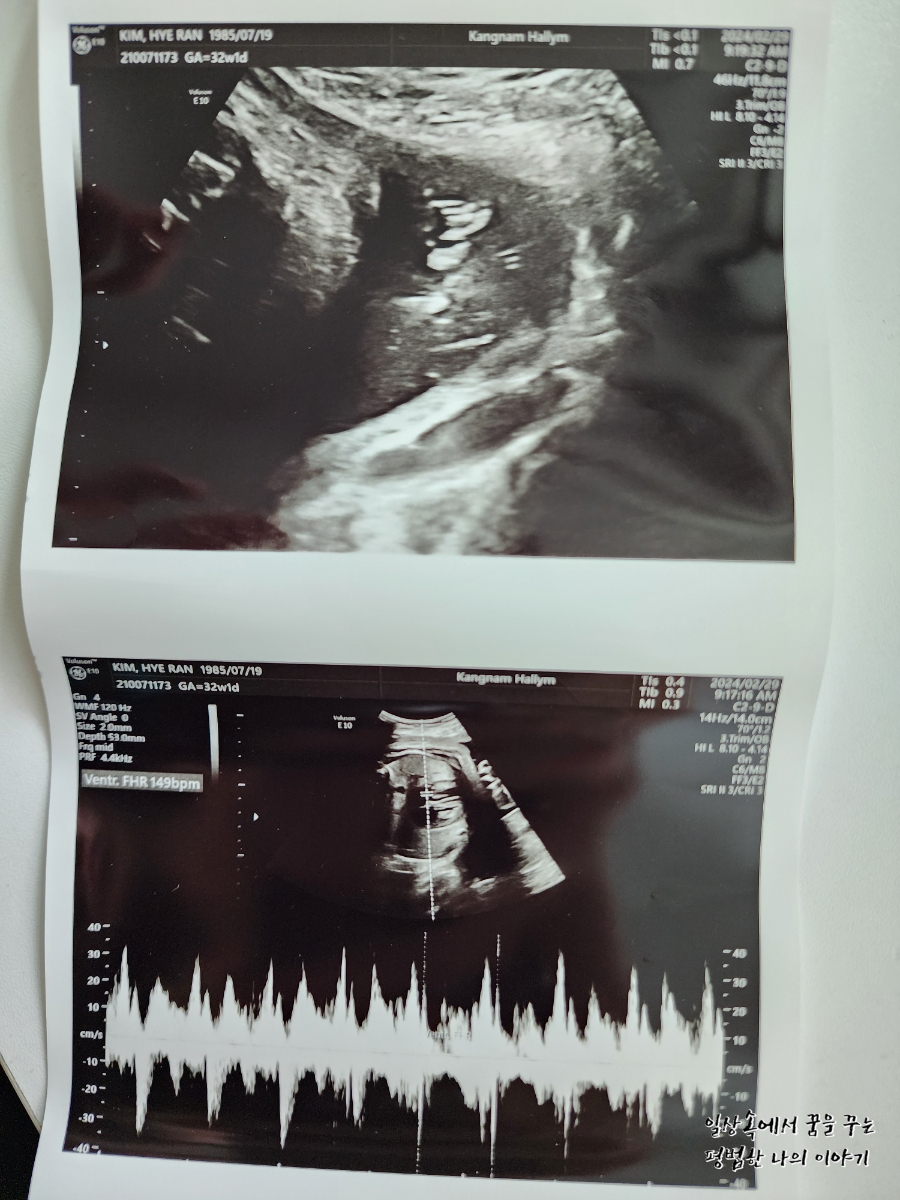

FHR(Fetal Heart Rate, 심장박동 수): 149bpm

3주 만에 방문한 병원에서 우리 딸내미는 무척이나 커져있었는데 지난번 정기검진에서는 길이랑 배 둘레만 원래 주차 수에 비해 컸다면 이번 정기검진에서는 전체적으로 2주 이상 커져있었다. 의사 선생님이 지금 주차 수에서는 알기 어렵고 막달이 돼봐야 알 것 같기만 왠지 4킬로는 훌쩍 넘을 것 같다고 하셔서 걱정이다. 무엇보다 배 둘레랑 머리둘레가 큰 편이라 분만의 어려움이 예상된다고 하시더라. 그래도 자연분만에 대한 생각은 아직까지 변함없긴 하지만 아직 시간이 많이 남았으므로 좀 더 지켜보기로... 그리고 이번 정기검진에서는 백일해 주사를 맞았다. 임산부는 태아를 위해서 첫째 때맞았더라도 추가로 맞아야 하고 남편과 친정엄마는 이미 첫째 때맞으셨기 때문에 추가로 다시 맞지 않아도 된다.